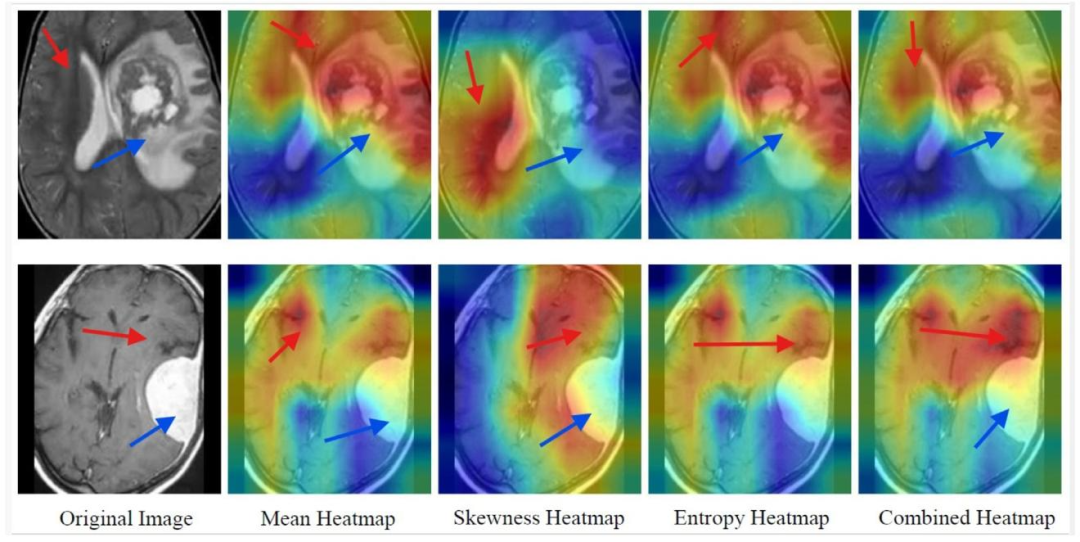

Fig. 6. SFMOV-based heatmap visualization showing a malignant image predicted as malignant (row 1) and a malignant image predicted as benign (row 2). Red arrows indicatethe healthy tissue/healthy interface, while blue arrows indicate the tumor/lesion.

图6. 基于SFMOV的热图可视化,展示了被预测为恶性的恶性图像(第1行)和被预测为良性的恶性图像(第2行)。红色箭头指示健康组织/健康界面,蓝色箭头指示肿瘤/病变区域。